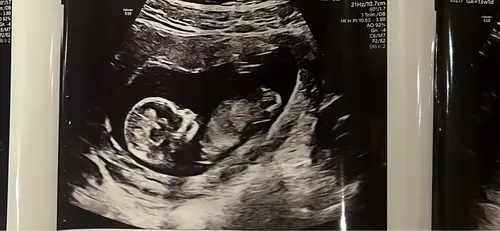

Wij afgelopen week ook de 13 weken echo gehad. Iemand enig idee ik zie het zelf helemaal niet namelijk 馃檭

Wat zal het worden meisje of jongetje鈽猴笍

Ik blij echt bij een meisje 馃槈

Ja ik dacht dus zelf echt dit ook (hoop het stiekem wel!) maar snap niet dat mensen jongen zeggen daardoor want die zie ik er niet in馃き馃ぃ